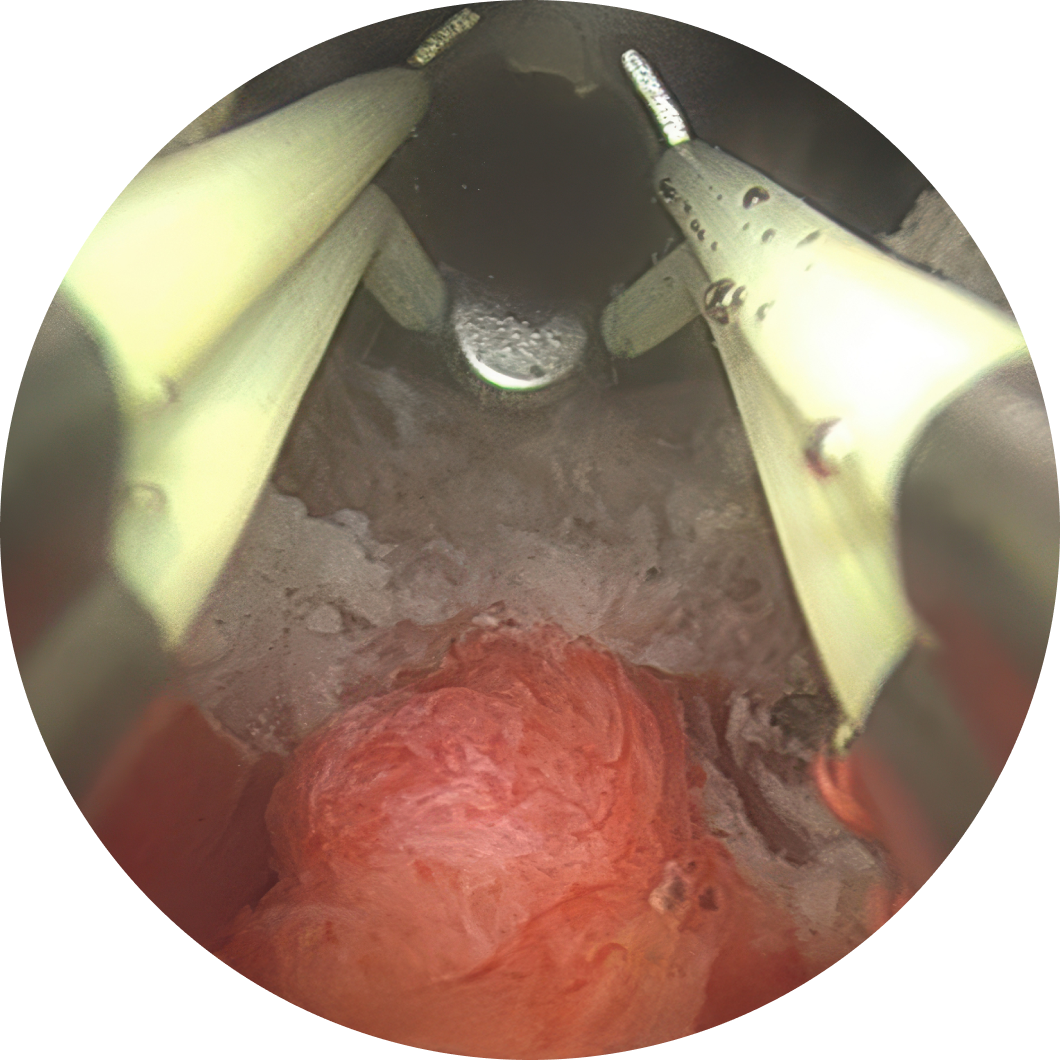

절제 부위를 정확히 지정합니다.

※ 관련 연구자료 : 369 cases till Nov.2024, Gilling P, et al. Two-Year Outcomes After Aquablation Compared to TURP: Efficacy and Ejaculatory Improvements Sustained. Advances in Therapy, April 2019

Bhojani Naeem, et al Aquablation for BPH in Large Prostates (80-150 mL): 1-Year Results. Urology Gold Journal, May 2019

Hood-Sparing Aquablation for BPH: A Novel Strategy to Preserve Antegrade Ejaculation in a Korean Single-Center Cohort

로봇 워터젯 수술(아쿠아블레이션)은 수술 시간이 7~15분으로 짧아 부담이 적습니다. 수술 당일 퇴원이 가능하며 많은 환자들이 치료 결과에 만족하고 있습니다.

일시적인 혈뇨, 배뇨통, 잔뇨감이 있을 수 있으나 대부분 수일 내에 호전됩니다. 열을 이용한 수술보다 성기능(발기, 사정 등) 보존률이 높은 편입니다.